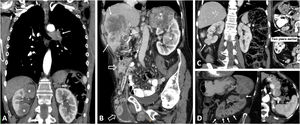

Clear cell renal cell carcinomas (ccRCC) with BAP1 somatic mutation. (A) Coronal CT in nephrographic phase. (B, C and D) Axial CT in corticomedullary phase. A 51-year-old woman with constitutional symptoms and a palpable left lumbar mass. CT shows a left renal tumour with highly infiltrative growth and heterogeneous enhancement (arrows), accompanied by a tumour thrombus in the left renal vein (hollow arrows), as well as pulmonary metastases (dashed arrows) and muscle metastases (arrowhead). Histological examination of the surgical specimen showed a histological grade 4 ccRCC with sarcomatoid features and BAP-1 somatic mutation.

PTEN syndrome-associated clear cell renal cell carcinoma (ccRCC). (A–D) PTEN syndrome. (A) Axial CT scan of the abdomen in the nephrographic phase. (B) Transverse section of ultrasound in B-mode of right hypochondrium. (C) Coronal cervical CT. (D) Photograph of the forehead. An 81-year-old male with haematuria. Physical examination revealed macrocephaly, a mass located at the base of the right side of the cervical region and evident papillomatous facial lesions (D). Imaging studies show several focal right renal lesions with intense enhancement and areas of necrosis (arrows). The largest of these is accompanied by a tumour thrombus, grade 4 in the Mayo clinic classification, which is echogenic and uptakes contrast (*). In addition, a large enhancing mass is visible near the right thyroid lobe (hollow arrows in C). A core needle biopsy was performed on the principal renal mass, which was diagnosed as ccRCC, and on the thyroid mass, which was diagnosed as follicular thyroid cancer, the most frequent histological subtype in this syndrome. The patient died before genetic testing was carried out, but they met the criteria for PTEN syndrome. (E) PTEN syndrome simulator. Coronal CT in nephrographic phase. A 79-year-old female. Lobulated renal mass with intense enhancement and central necrosis (arrows) together with a similar mass near the left thyroid lobe. While PTEN syndrome was suspected, the histological diagnosis was ccRCC with thyroid metastasis. The patient did not meet any other clinical criteria for PTEN.